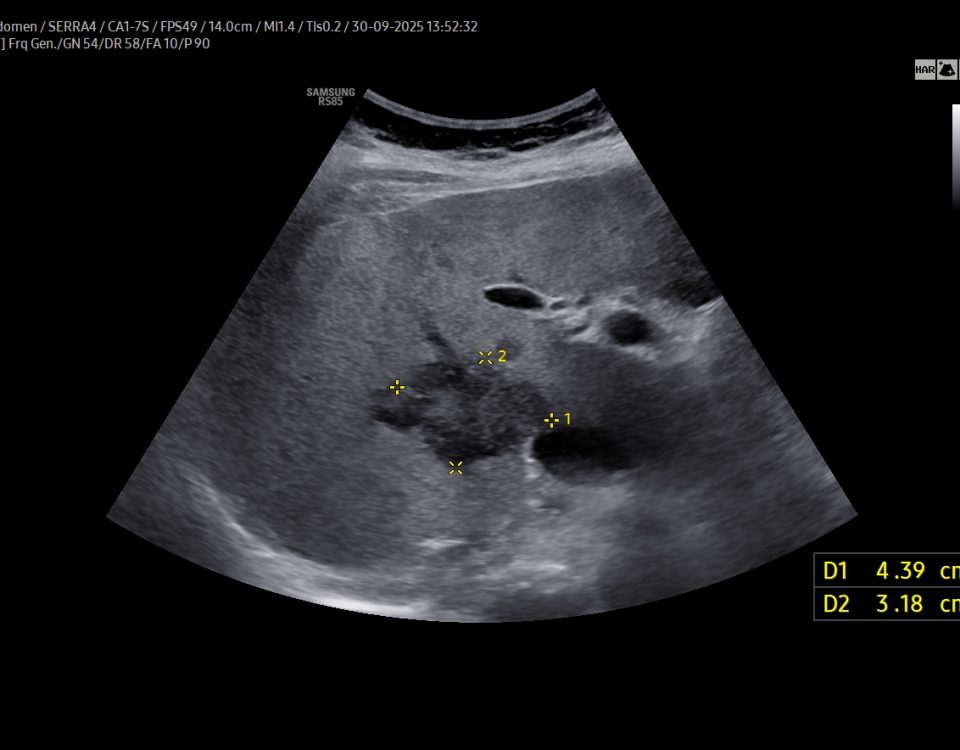

FIGURE 1 and VIDEO 2: Ultrasonography demonstrates the presence of free fluid within the peritoneal recesses, predominantly in the perihepatic and subhepatic regions (yellow asterisks). The fluid appears mildly echogenic, suggestive of inflammatory exudate rather than simple transudate. The duodenal bulb (D1 segment) is thickened and edematous. The area outlined in red demonstrates multiple hyperechoic foci with reverberation artifacts consistent with extraluminal free gas, adjacent to a focal mucosal wall defect. These findings are highly suggestive of a perforated duodenal ulcer.

The duodenal bulb (D1 segment) is thickened and edematous. The area outlined in red demonstrates multiple hyperechoic foci with reverberation artifacts consistent with extraluminal free gas, adjacent to a focal mucosal wall defect. These findings are highly suggestive of a perforated duodenal ulcer.